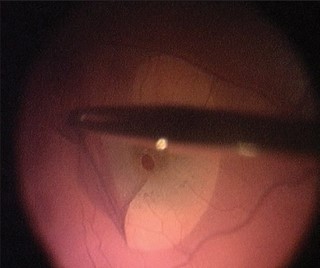

Não é possível prevenir o buraco de mácula. O tratamento é feito através da cirurgia de vitrectomia com remoção de uma membrana chamada membrana limitante interna, que diminui as trações tangenciais e permite fechamento do buraco macular.

A cirurgia não é de urgência, mas não deve ser postergada, pois o buraco de mácula tende a aumentar com o tempo ou tornar-se atrófico, diminuindo a chance de sucesso cirúrgico.